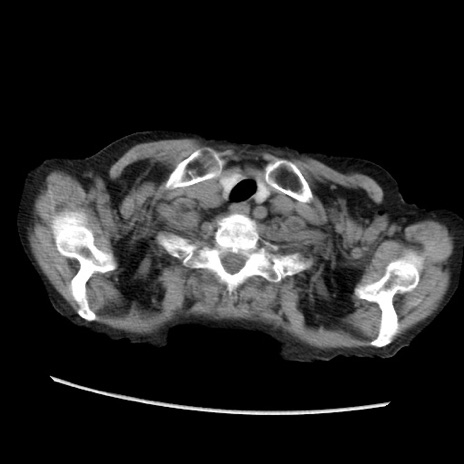

症例31(横断像)

【症例】80歳代 女性

【主訴】腹部膨満感

【現病歴】他院にて肝硬変にてフォロー中。1週間前から便秘、腹部膨満感、臍部腫瘤あり受診となる。

【既往歴】肝硬変

【身体所見】腹部膨隆あり、皮膚変化なし、疼痛なし。

【データ】WBC 4600、CRP 0.25